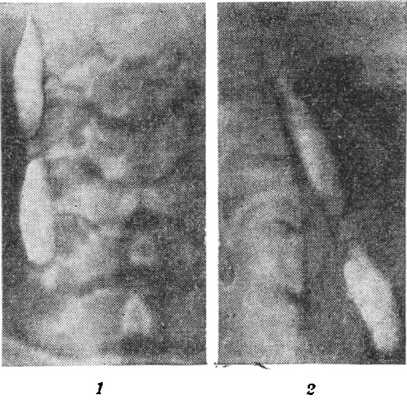

Рис. 1. Боковая бранхиогенная киста, заполненная йодолиполом (на рисунке — светлые пятна): 1 — рентгенограмма в передней проекции; 2 — рентгенограмма в боковой проекции.

На обычных и послойных рентгенограммах шеи Б. к. не дает ясного изображения. Лишь при значительной величине кисты может определяться изменение нормальной структуры мягких тканей шеи. Рентгенологическое исследование приобретает важную роль при наличии наружного свища, обусловленного Б. к. В этих случаях через наружное свищевое отверстие вводят контрастное вещество, нагретое до t° 30—33°. Введение контрастной массы облегчается при наличии второго, внутреннего свища или при поверхностно расположенной кисте. После окончания введения производят переднюю и боковую рентгенограммы шеи (рис. 1) в сидячем положении исследуемого.

Фистулограммы позволяют установить направление, калибр и протяженность свищевого хода, местоположение, форму и размеры Б. к. и ее топографические отношения с органами шеи (глоткой, гортанью, трахеей). Эти данные необходимы для точной топической диагностики и выбора метода оперативного вмешательства.